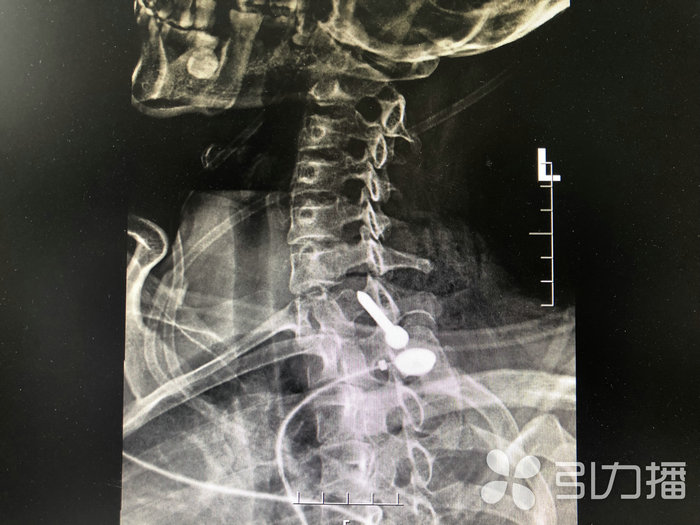

王女士立即被120送到了苏州科技城医院医院急诊部,快速完成颈部CT和X线检查。该院普外一科主任医师王奇与骨科副主任医师徐希斌立即赶往急诊进行会诊。

专家看到,王女士右颈部有一长约6厘米的伤口,伤口处还外露着一根铁钉,铁钉尖头朝外,创口内还不停出血,右侧上肢活动受限。影像资料未见明确的颈部骨结构破裂。王奇表示,需马上对其进行颈部手术探查,明确损伤情况,取出异物。

“因为颈部被高速飞行的铁钉损伤,无法确认内部受伤情况,手术必须把颈部重要血管、神经、肌肉组织显露,查看有无损伤及仔细探查伤道。经判断,王女士的右臂丛神经损伤,颈外静脉断裂,颈部肌肉多处断裂,伤道紧靠颈总动脉。但凡稍有偏差,后果将不堪设想。”王奇小心翼翼将钉子取了出来,足足有5公分长。最后经过颈部清创缝合,手术顺利,术后生命体征平稳。